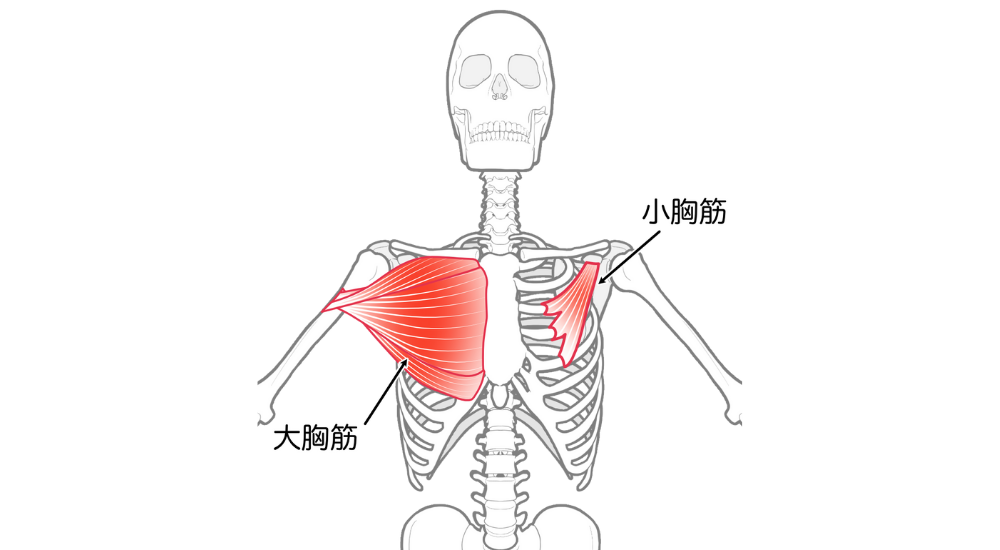

- 大胸筋・小胸筋: 胸の前面にある筋肉。巻き肩で短縮・硬化しやすく、肩甲骨を前方に引っ張り固定してしまいます。